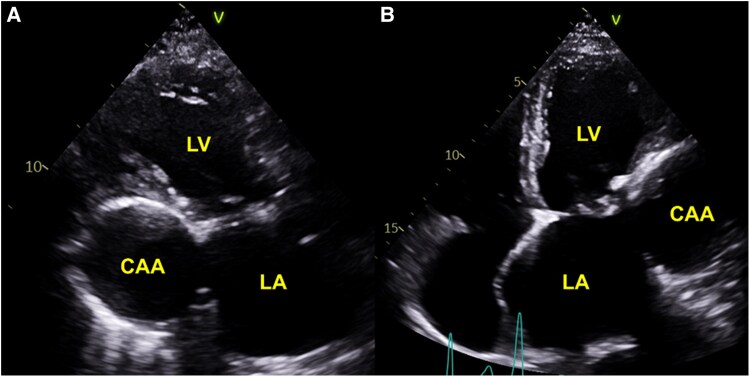

Coronary artery aneurysm (CAA) is a rare, dilated segment of the coronary artery. Phenotypically, it can have different morphologies, patterns, content, and affected vessels, making multimodality invasive and noninvasive imaging play a significant role in its evaluation. In this review article, we discuss in depth the contemporary perspectives in pathophysiology, epidemiology, clinical presentation, multimodality imaging evaluation, treatment strategies (medical, percutaneous and surgical) and outcomes of CAA. CAA is predominantly associated with coronary atherosclerotic diseases and/or autoimmune vasculitis conditions including Kawasaki disease. It can present with various clinical manifestations, from an incidental finding to myocardial infarction and life-threatening complications. While coronary angiography has been the gold standard to detect CAA, noninvasive modalities including coronary computed tomography have increasingly been utilized given its high resolution for anatomical depiction of the vessels and relations to surrounding structures. We suggest a stepwise approach to the assessment and clinical decision-making in the management of CAA. Pharmacological strategies include risk factor control and secondary prevention. For obstructive ischaemic presenting aneurysms, percutaneous is pursued, while larger or multi-vessel obstructive lesions are typically managed with coronary surgery.